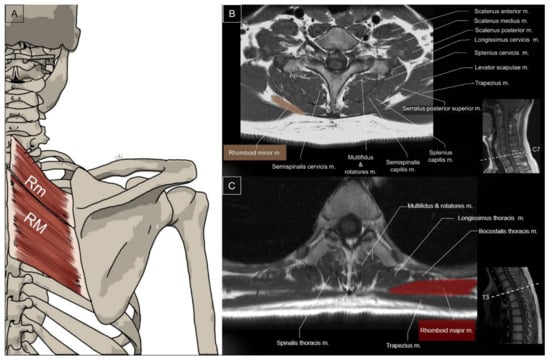

2.2. Rhomboids

2.2.1. Anatomy

2.2.2. Sonographic Scanning

2.2.3. Clinical Relevance